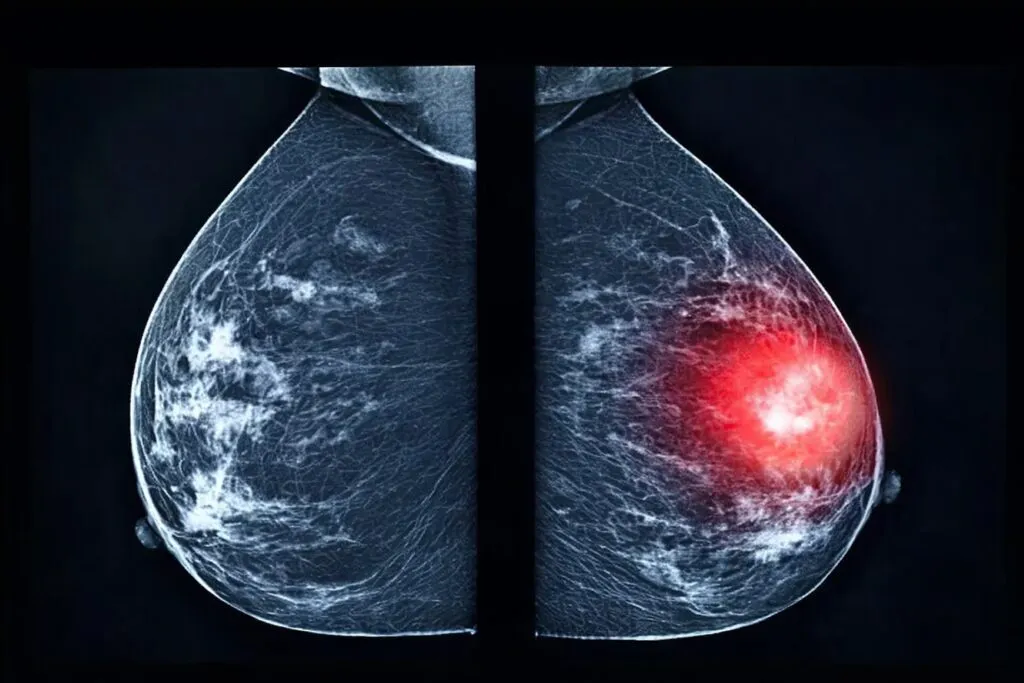

Detectar células tumorales en circulación ha sido uno de los principales desafíos técnicos en el manejo clínico del cáncer de mama triple negativo, un subtipo altamente agresivo que escapa a los tratamientos hormonales convencionales. Investigadores del Baylor College of Medicine reportaron un avance sustancial en esta dirección: la identificación de cuatro nuevas proteínas de superficie que permiten localizar con mayor precisión estas células mientras se desplazan por el torrente sanguíneo.

La investigación, publicada en enero de 2026 en Cancer Research Communications, confirma que los nuevos biomarcadores superan en sensibilidad a los utilizados hasta ahora. Esto representa una mejora concreta en el monitoreo de la enfermedad, permitiendo un seguimiento más exacto de la progresión tumoral y la respuesta terapéutica en tiempo real.

Los experimentos iniciales en modelos murinos fueron seguidos por validaciones clínicas en muestras de pacientes con cáncer metastásico. En estos casos, las células tumorales circulantes resultaban invisibles con marcadores estándar, pero se volvieron detectables con la nueva combinación. Esto representa un cambio de paradigma para las plataformas de biopsia líquida, cada vez más relevantes en oncología de precisión.